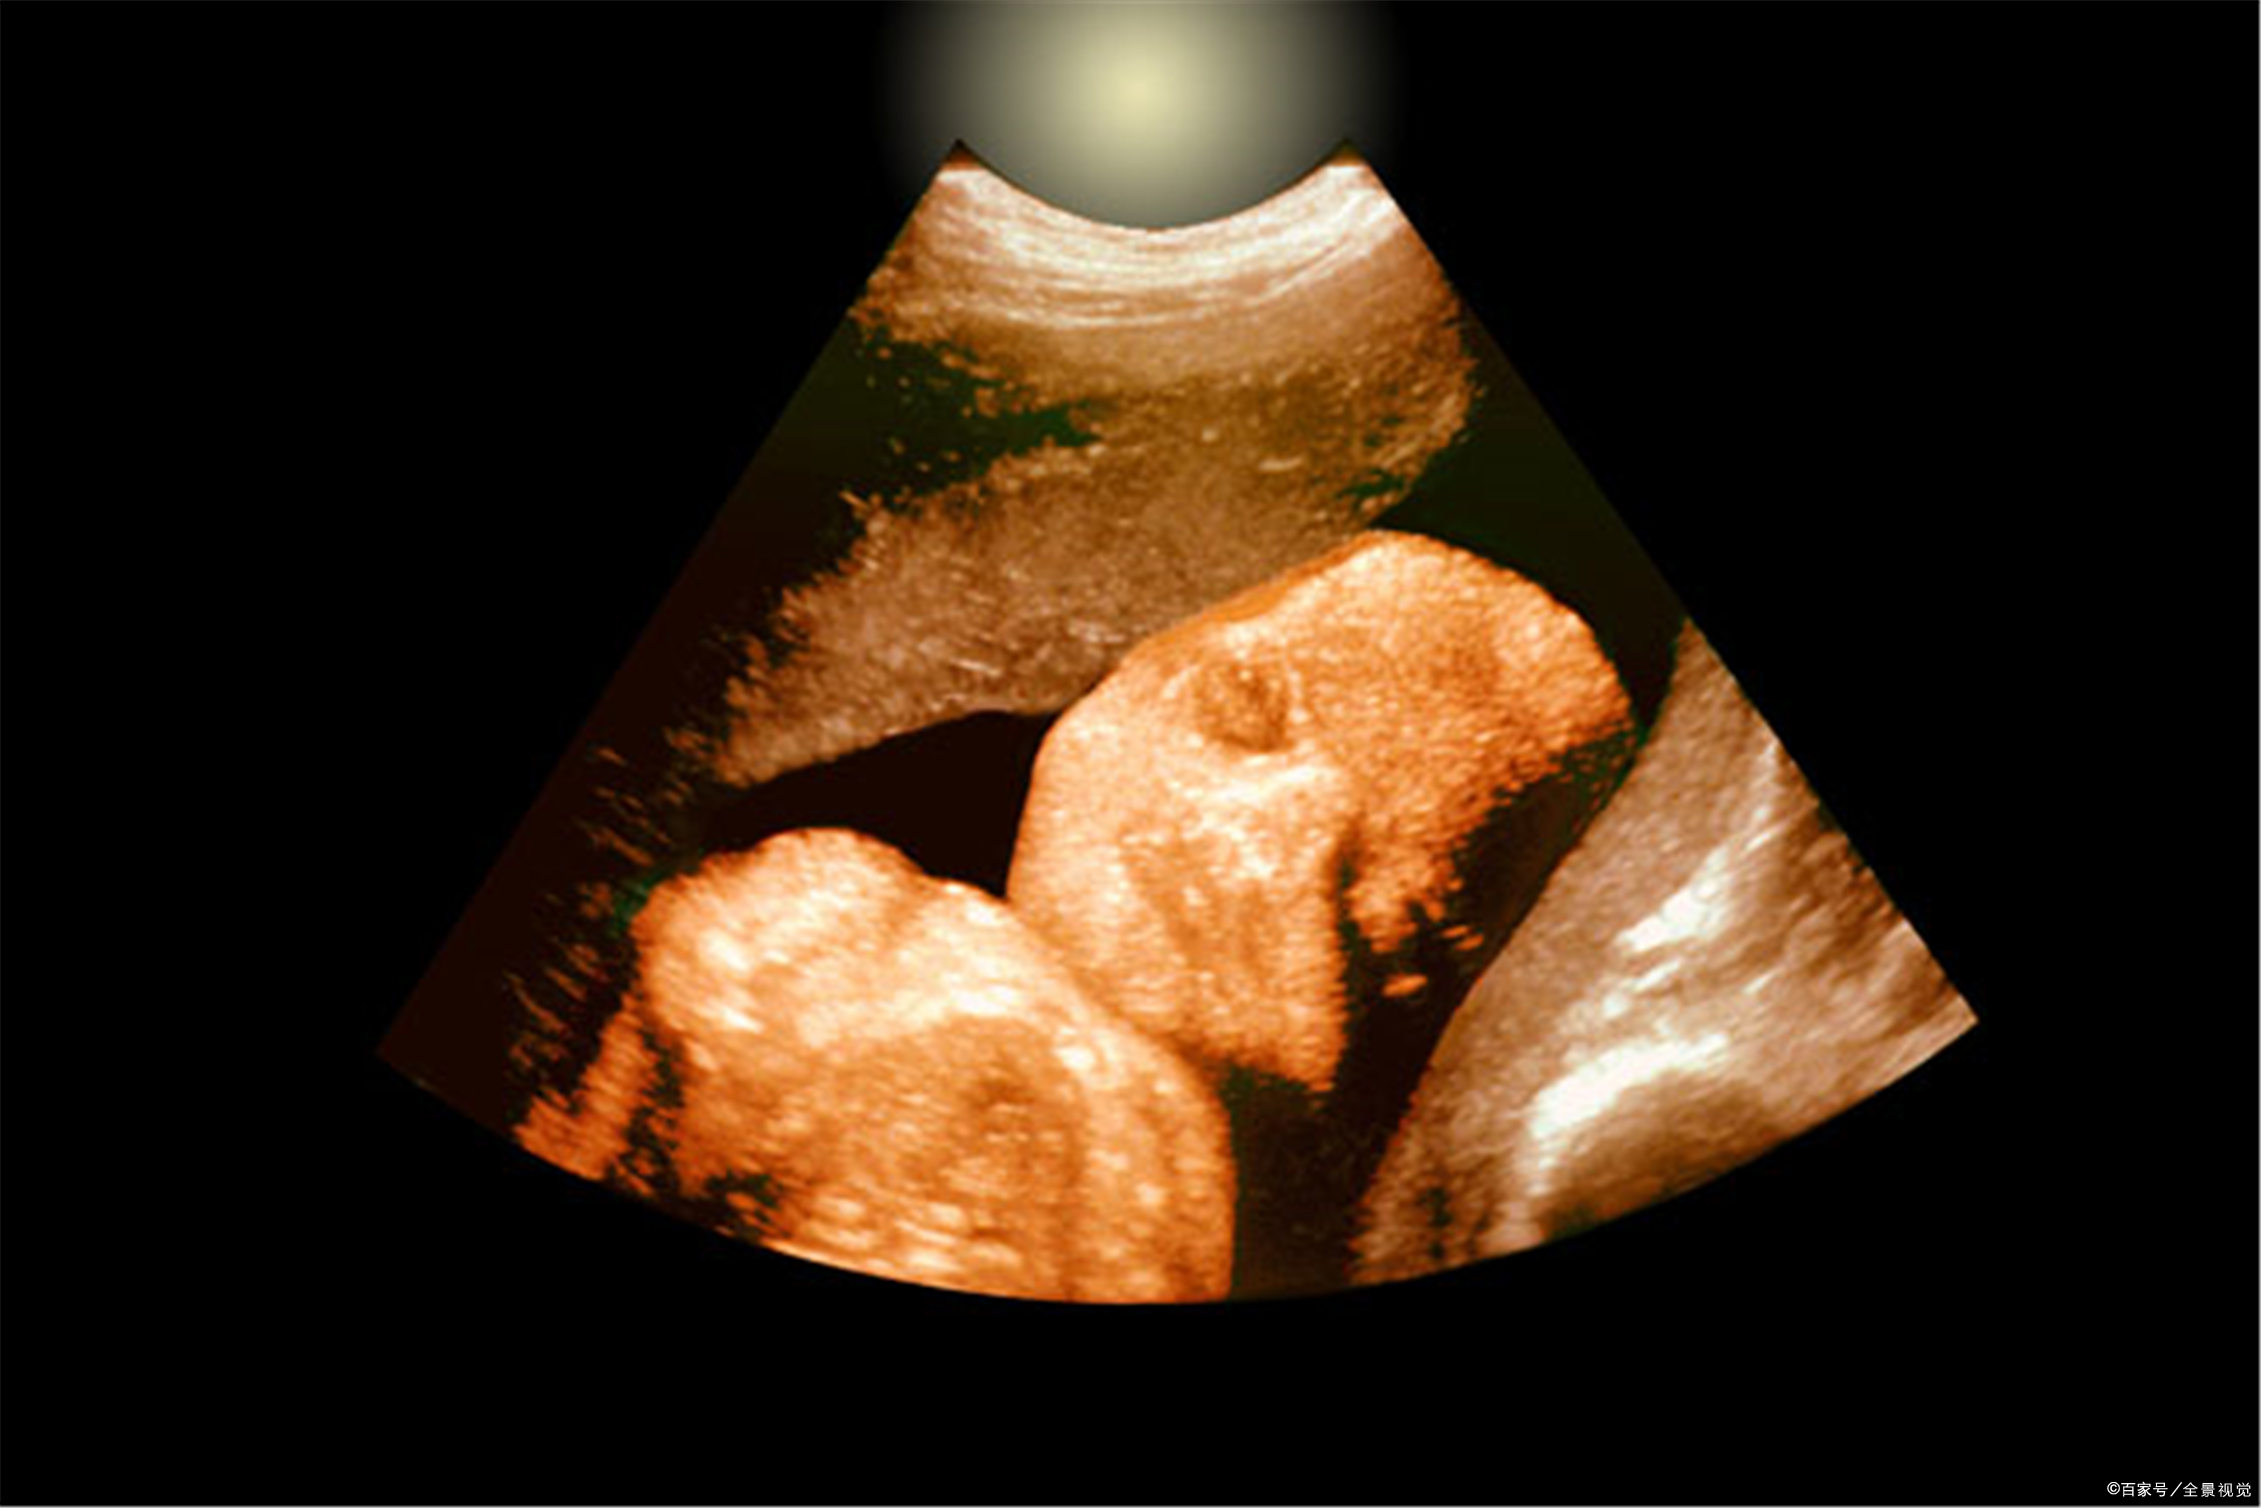

P11 子宫内的胎儿、脐带和胎盘关系的示意图知识补充

1.胎儿生活在母体内,胎儿生长发育过程中所需要的各种营养物质,都是通过胎盘从母体中获得的。如果孕妇喝酒、吸烟(包括被动吸烟)或者吃了某些药品,酒精、*草烟**和这些药品中的有害物质,就会通过胎盘和脐带到达胎儿的体内,对胎儿的生长发育产生不良影响。